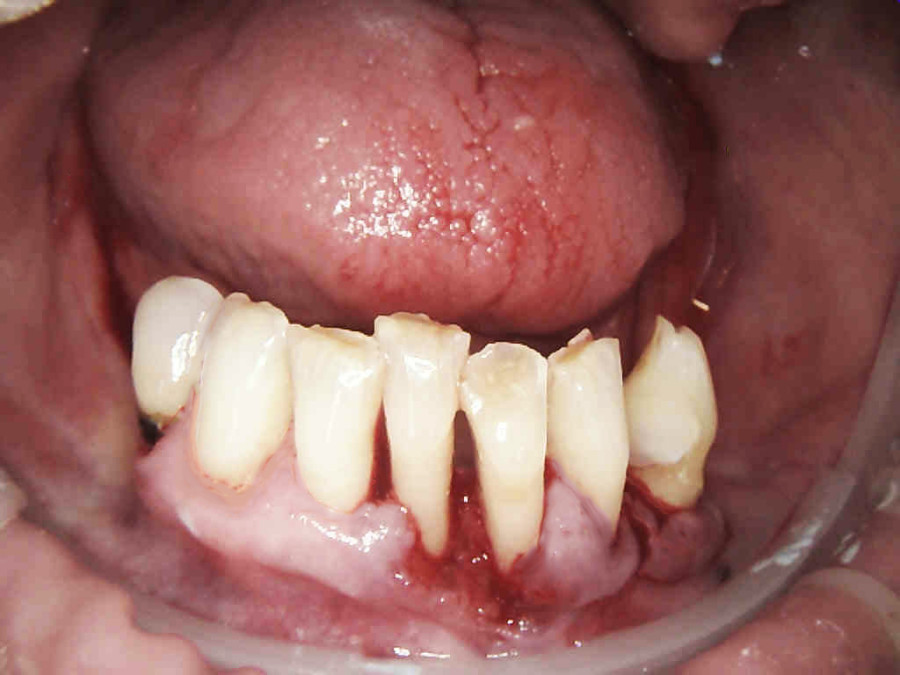

Pacjentka lat 65, zgłosiła się do stomatologa na konsultację, ponieważ niepokoiła ją ruchomości zębów. W pierwszej kolejności została skierowana na wizyt higienizacyjną. Bezzębie w łuku górnym zaopatrzone było całkowitą akrylową protezą, w łuku dolnym pacjentka nie użytkowała żadnego uzupełnienia. Pacjentka niepaląca.

Postępowanie rozdzielono na dwie wizyty. Badaniem klinicznym, oceniając wskaźniki periodontologiczne, uzyskano wartości API 100%, PBI 100% świadczące o konieczności poprawy higieny i procesie zapalnym dziąseł, duże złogi kamienia nad i poddziąsłowego, bardzo obfity biofilm, pogłębione wszystkie kieszonki dziąsłowe, ciężkie zapalenie dziąseł, ruchomości zębów dolnych III stopnia, duży zanik kości. Badanie kliniczne błony śluzowej jamy ustnej nie wykazało zmian patologicznych.